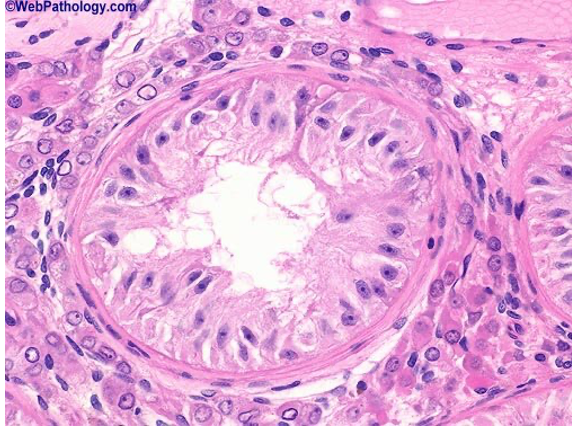

What is shown here? (testis)

Vas diferens - high power picture